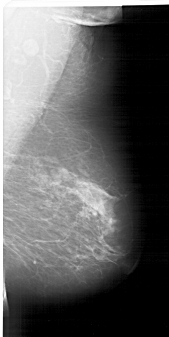

A_1335_1.LEFT_CC

LEFT_CC LINES 6706 PIXELS_PER_LINE 3421 BITS_PER_PIXEL 12 RESOLUTION 43.5 OVERLAY

FILE: A_1335_1.LEFT_CC.OVERLAY

TOTAL_ABNORMALITIES 1

ABNORMALITY 1

LESION_TYPE MASS SHAPE OVAL MARGINS OBSCURED

ASSESSMENT 3

SUBTLETY 3

PATHOLOGY BENIGN

TOTAL_OUTLINES 1

BOUNDARY